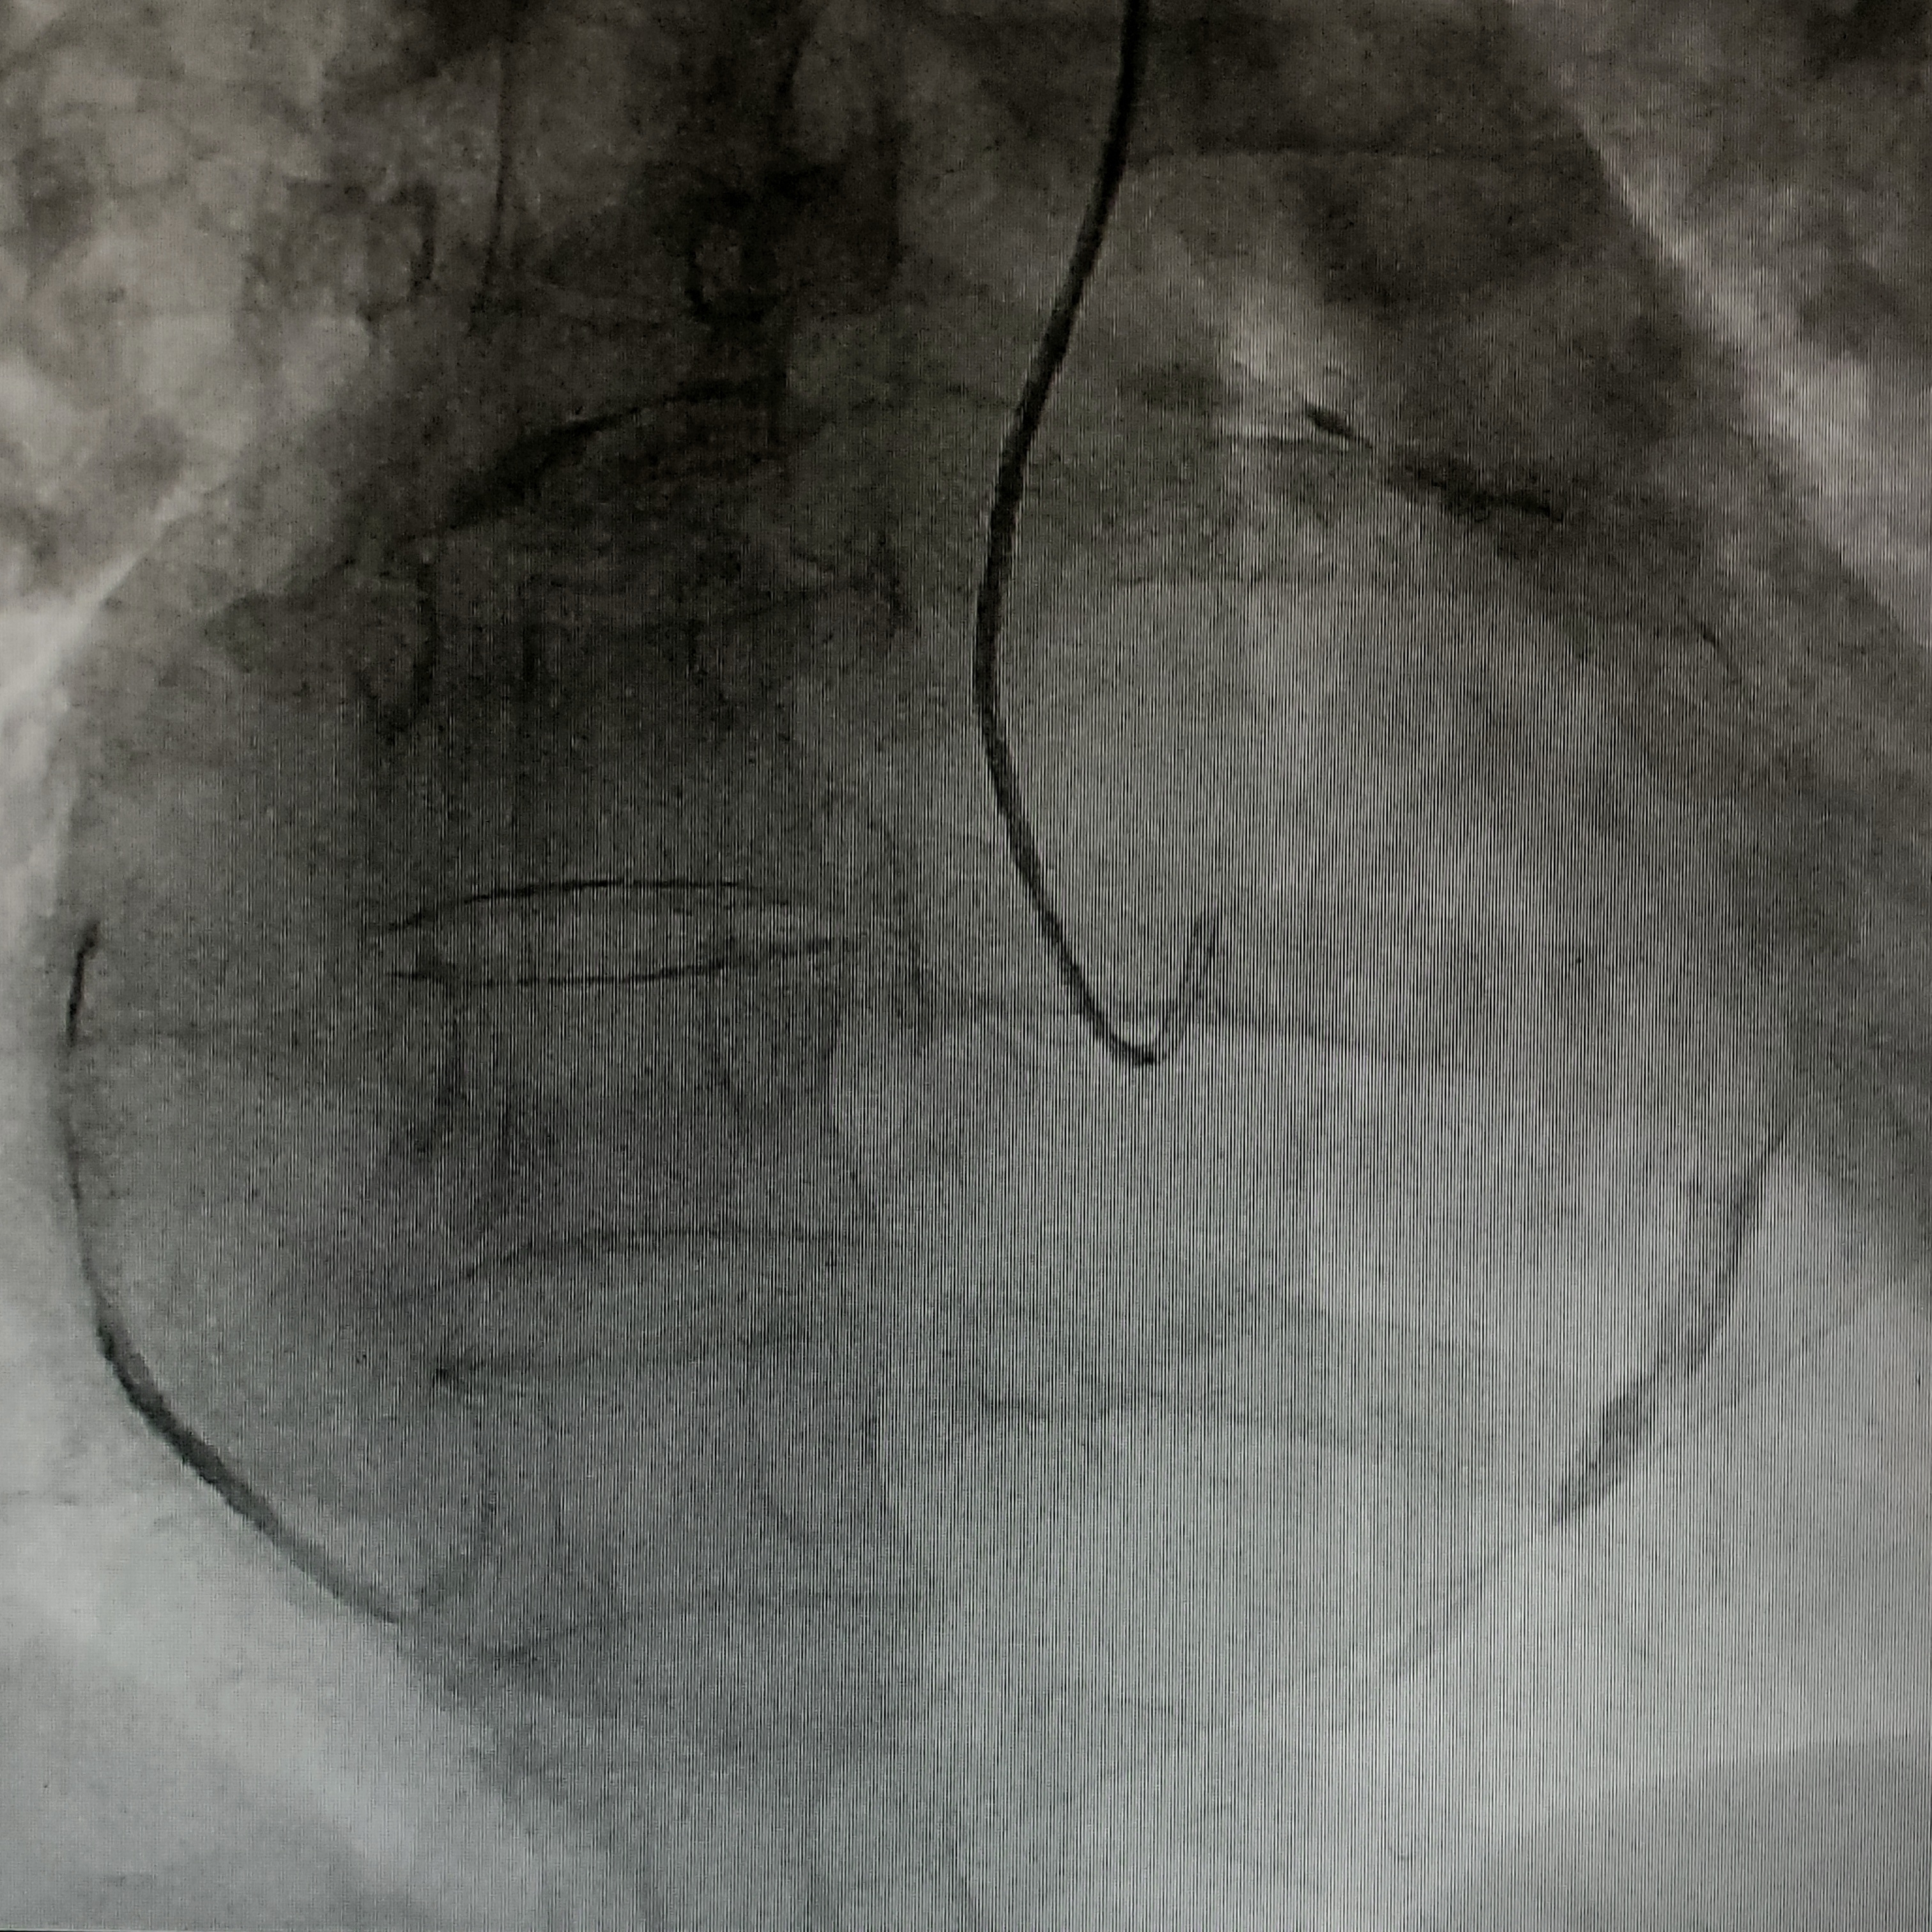

Porcelain Left Atrium as seen on Coronary Angiogram

Clinical Case: A 50-year-old female with a history of rheumatic heart disease, previously treated with closed mitral valvuloplasty and percutaneous transvenous mitral commissurotomy, presented with severe dyspnea and heartburn. She was admitted for a coronary angiogram in preparation for a double valve replacement. The angiogram revealed normal coronary arteries but significant calcification of the left atrium. Transthoracic echocardiography confirmed severe mitral stenosis, mild mitral regurgitation, moderate aortic regurgitation, and a grossly dilated left atrium, with preserved left ventricular systolic function. Following an uneventful recovery, the patient was discharged and scheduled for the planned valve surgeries.